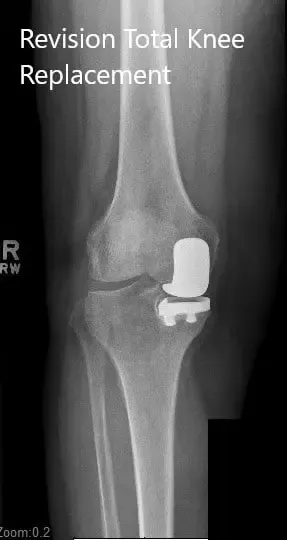

Radiografía preoperatoria de la rodilla derecha en vistas anteroposterior y lateral

DIAGNÓSTICO PREOPERATORIO: Reemplazo unilateral medial de rodilla fallido.